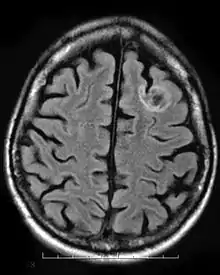

A dysembryoplastic neuroepithelial tumour is commonly diagnosed in patients who are experiencing seizures with magnetic resonance imaging (MRI), electroencephalogram (EEG).[4] A DNT is most commonly diagnosed in children who are experiencing seizures, and when given medication do not respond to them. When an MRI is taken there are lesions located in the temporal parietal region of the brain.[4]